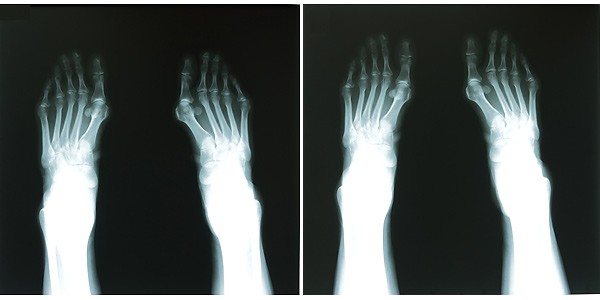

| 外反母祉対策靴下 女性の約4割が悩んでいるという外反母祉(がいはんぼし)。これを患うと前後左右の重心バランスがくずれ歩行に悪影響を引き起こしたりします。また、歩くのがおっくうになり、活動意欲も低下します。 外反母址対策靴下は、着用すると外反母祉角が減少する構造になっております。 テーピングやサポーター、矯正する器具とも違うので手軽に装着でき、長時間の着用でも違和感がありません。 また靴を着用することもできます。 共同開発をした広島大学大学院保健学研究科・浦辺幸夫教授の調査では(60歳以上の女性15名を対象)、着用2か月後には外反母祉角度の低下が認められました。 外反母祉角が減少することにより重心のバランスも改善します。 高齢者を転倒から守り、活動意欲の低下が助長する廃用性の身体機能低下も防げると期待されています。 30代女性都内、藤本クリニックにてレントゲン撮影 ![]()

●担当の医師、曰く外反母趾とは 中足骨(ちゅうそくこつ)、その上の基節骨(きせつこつ)が亜脱臼している状態とのこと。 中足骨は、ちょうど親指の付け根の丸くなっている箇所で基節骨は、写真では、その上に乗っかっております。 未着用時では、これらの位置関係が、少し外れたようになっているのがわかります。 靴下着用時は指が外に広がっていることも分かりますが、担当医師によると、専門家は中足骨と基節骨の位置関係を重視しています。 基節骨が中足骨にしっかりと乗った状態に戻っているのが分かります。 担当医師も、これは想像以上に効果のある靴下ですねと感心しておられました。 |